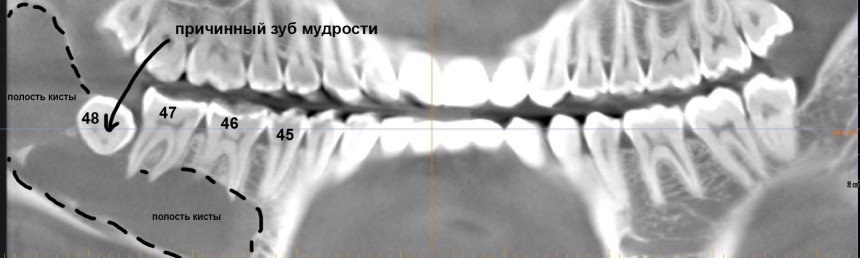

Но самое неприятное, что можно ждать от ретинированных зубов мудрости — это кисты.

Их источником является фолликул, окружающих зачаток зуба. Когда зуб прорезывается, фолликул исчезает, но в случае ретенции он сохраняется и может служить источником опухолей и кист.

Иногда — достаточно больших и весьма опасных для здоровья.

И хотя всё это вполне себе лечится, согласитесь, что лучше не доводить себя до такого состояния.